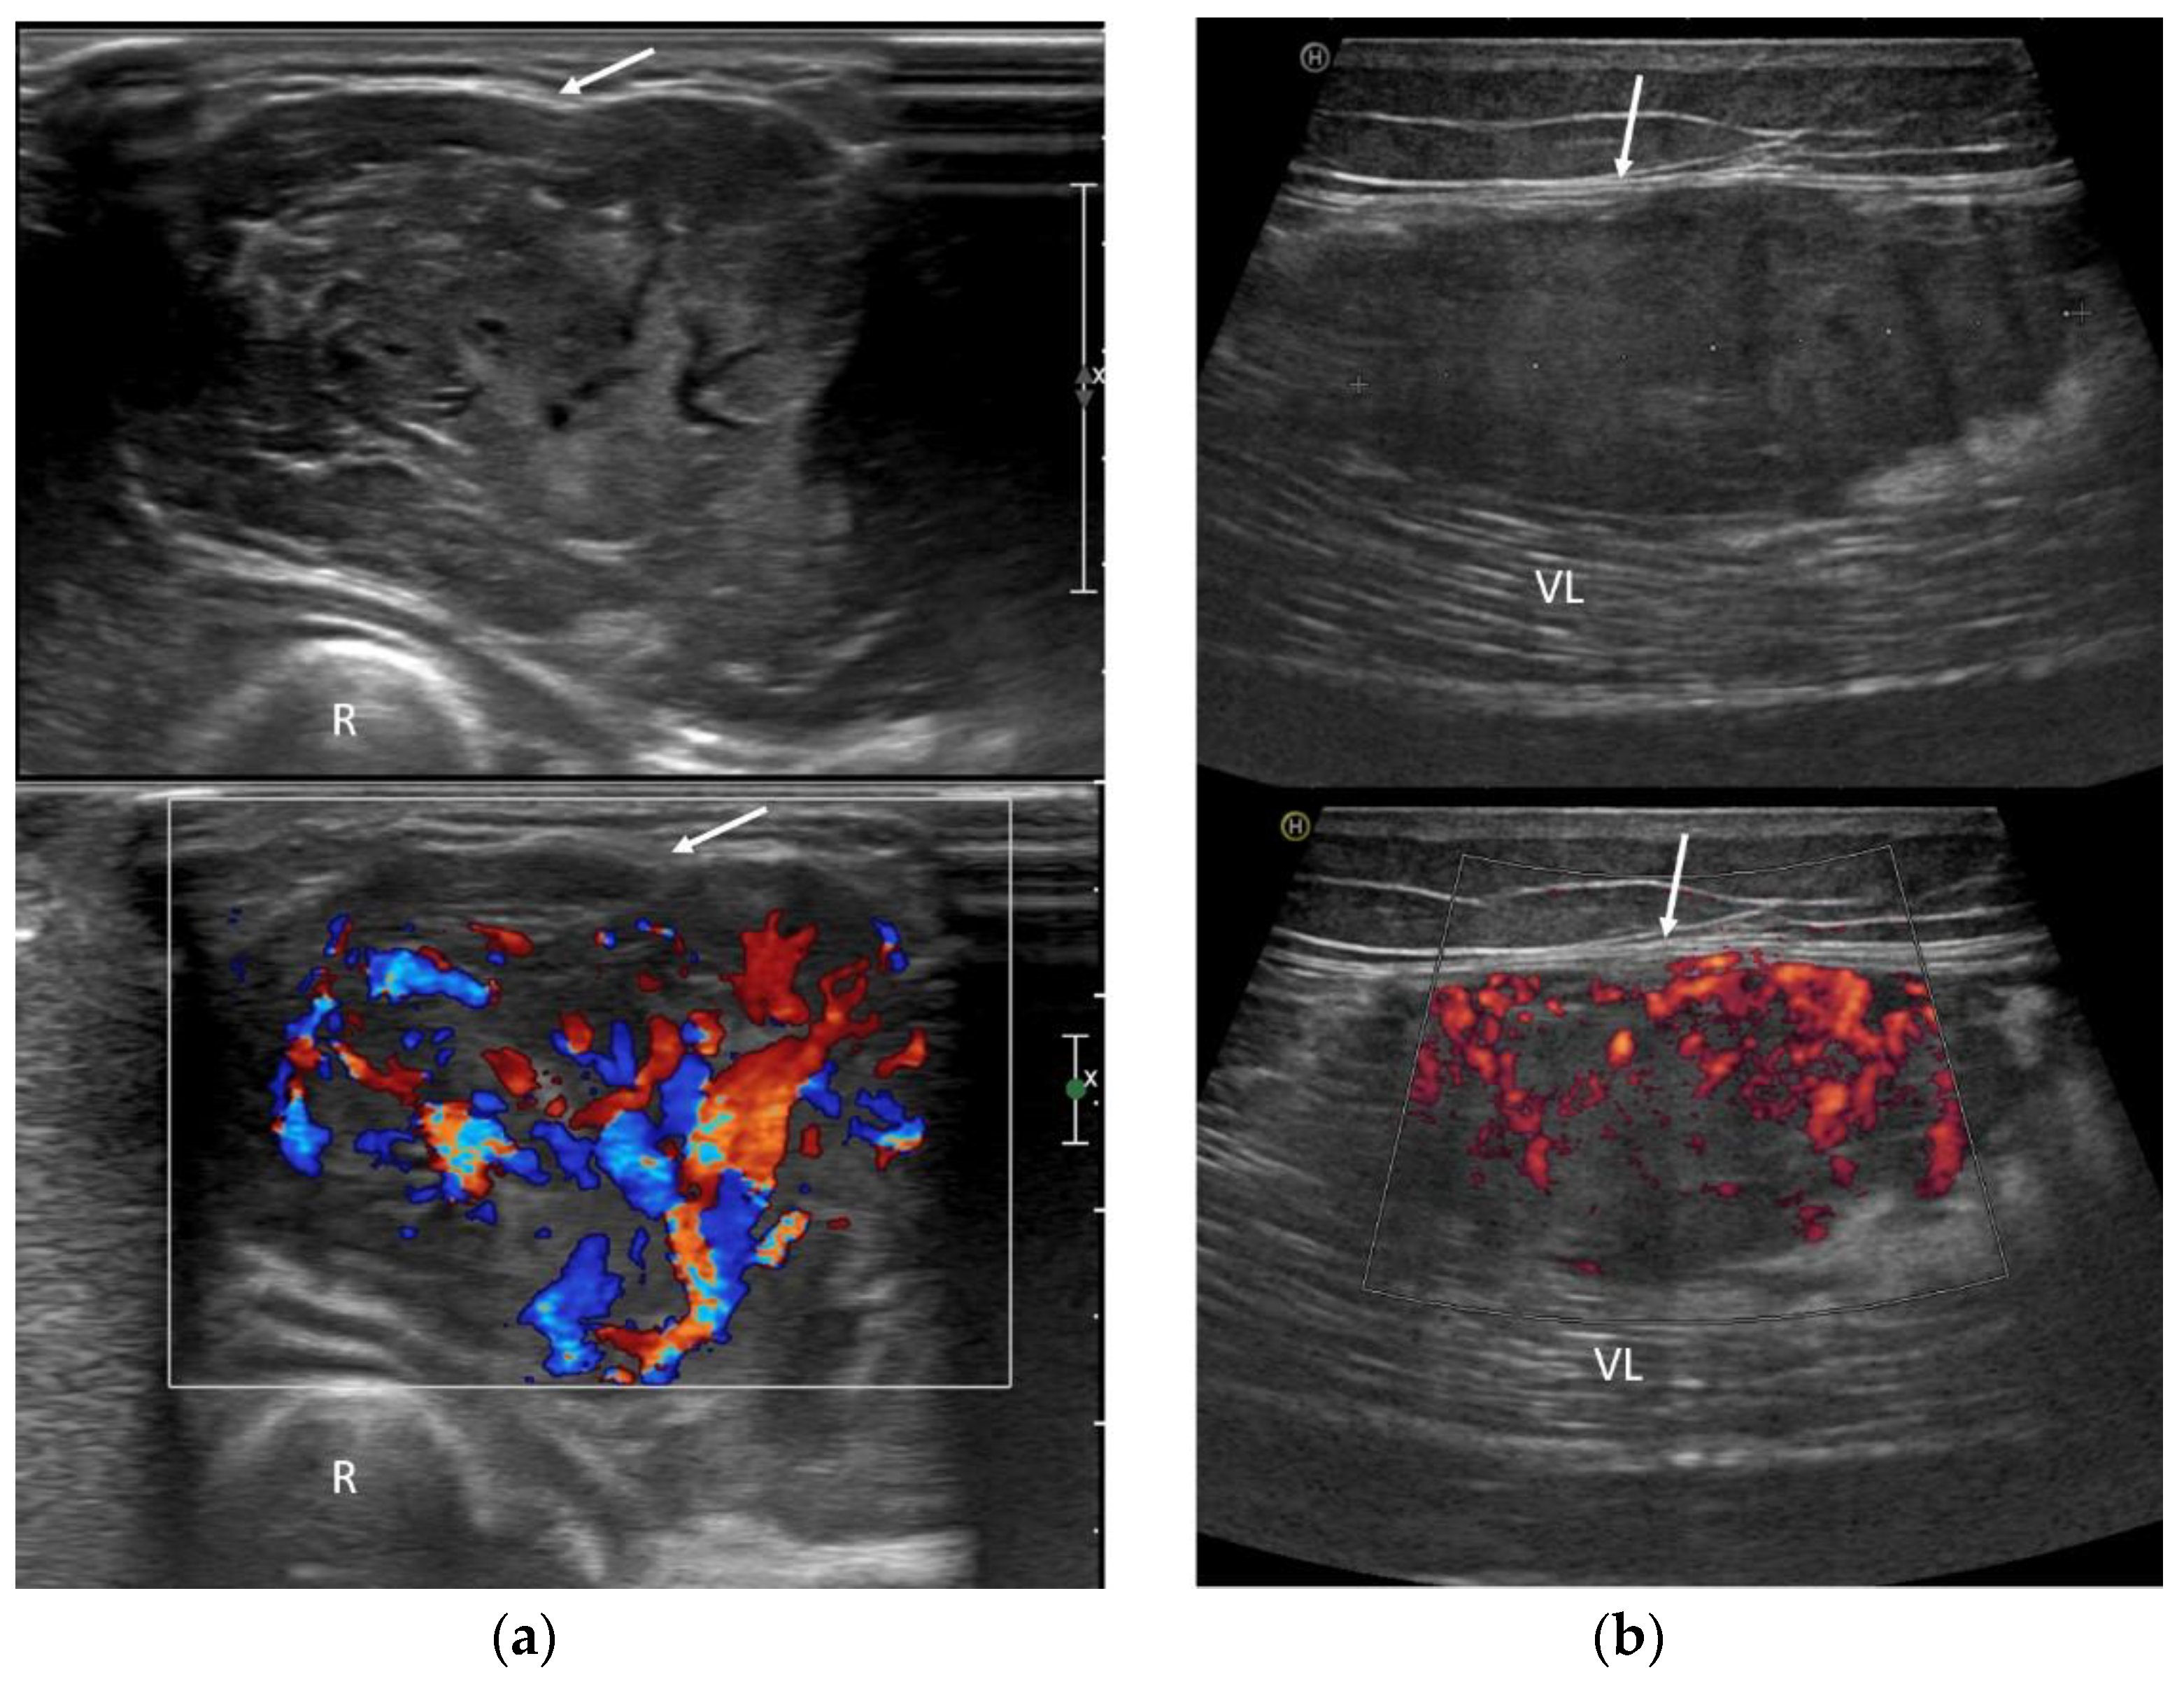

3.3. Ultrasound Features

- Inhomogeneous, mainly hypoechoic US pattern with strong internal vascularization at Color-Doppler evaluation

| Deep-seated location | Well-defined borders | Intra and peritumoral flow-voids | Low density on unenhanced scans |

| Peritumoral feeding vessels | Inhomogeneous hypoechoic pattern | Slightly high SI on T1w | - |

| Strong internal vascularization | Arteriosus Doppler sonographic pattern inside peritumoral vessels | High SI on T2w | - |